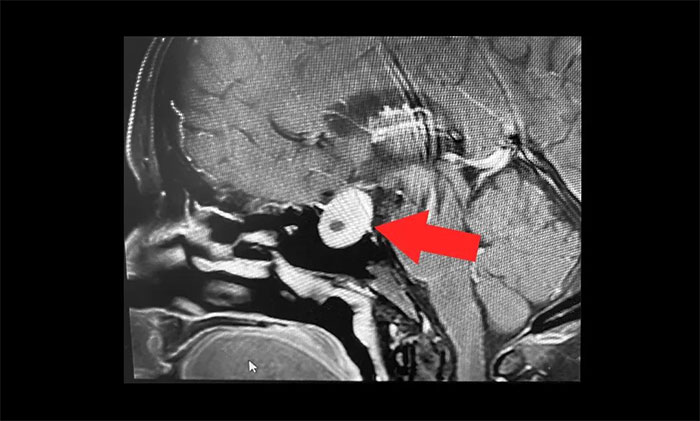

▲ 雖然無功能性垂體瘤并不具有內(nèi)分泌功能,但由于瘤體較大,已經(jīng)壓迫視神經(jīng),丘腦垂體,如果不手術,任其發(fā)展將可能導致患者視力下降、視野缺損,甚至失明。